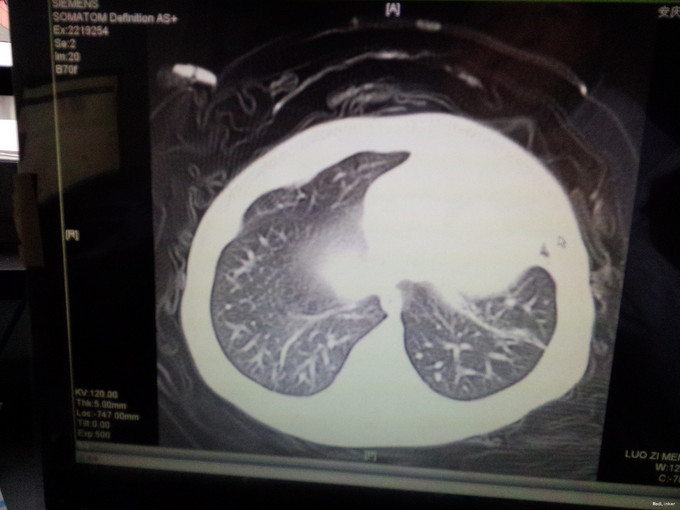

女,4月,咳嗽4-5天,加重一天。4-5天出现咳嗽,不发热,在诊所就诊予以对症处理(具体用药不详),疗效不佳,咳嗽症状加重,气促明显,近2天患儿吃奶差,无呕吐,大便呈稀水样改变。体检:神清,精神差,呼吸急促50次i/分,HR140次/分,两肺可闻及明显的湿罗音,心脏未闻及明显病理性杂音。肺部CT提示肺不张,心脏B超提示室间隔缺损(基底部)。血RT:WBC16.87*109/l,免疫球蛋白水平低.

呼吸急促50次i/分,HR140次/分,两肺可闻及明显的湿罗音,心脏未闻及明显病理性杂音。肺部CT提示肺不张,心脏B超提示室间隔缺损(基底部)。血RT:WBC16.87*109/l,免疫球蛋白水平低.